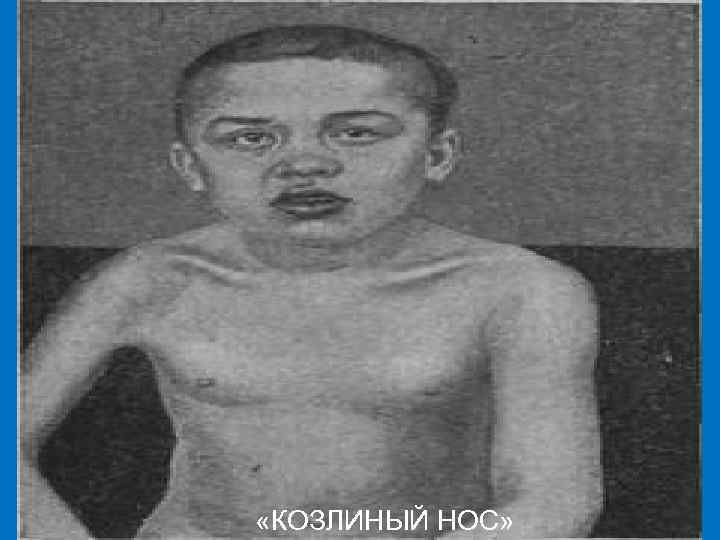

При отсутствии лечения возможно изъязвление слизистой оболочки. При разрушении хрящевой и костной основы носа наступает западение и расширение переносицы, нос приобретает «седловидную» форму и напоминает «козлиный»

«КОЗЛИНЫЙ НОС»

«КОЗЛИНЫЙ НОС»

«КОЗЛИНЫЙ НОС»

Вероятные признаки Рубцы Робинсона–Фурнье – следствие глубоких трещин кожи в области диффузной папулёзной инфильтрации, перенесенной в грудном возрасте. Они представлены тонкими белесоватыми полосками рубцовой ткани, пересекающие красную кайму губ и продолжаю-щиеся на окружающую кожу, особенно в области углов рта. Седловидный или «козлиный» нос – результат разрушения носовой перегородки и хряща при специфическом рините. На слизистой оболочке носа нередко наблюдается характерное хр. поражение в виде озены (зловонный насморк).